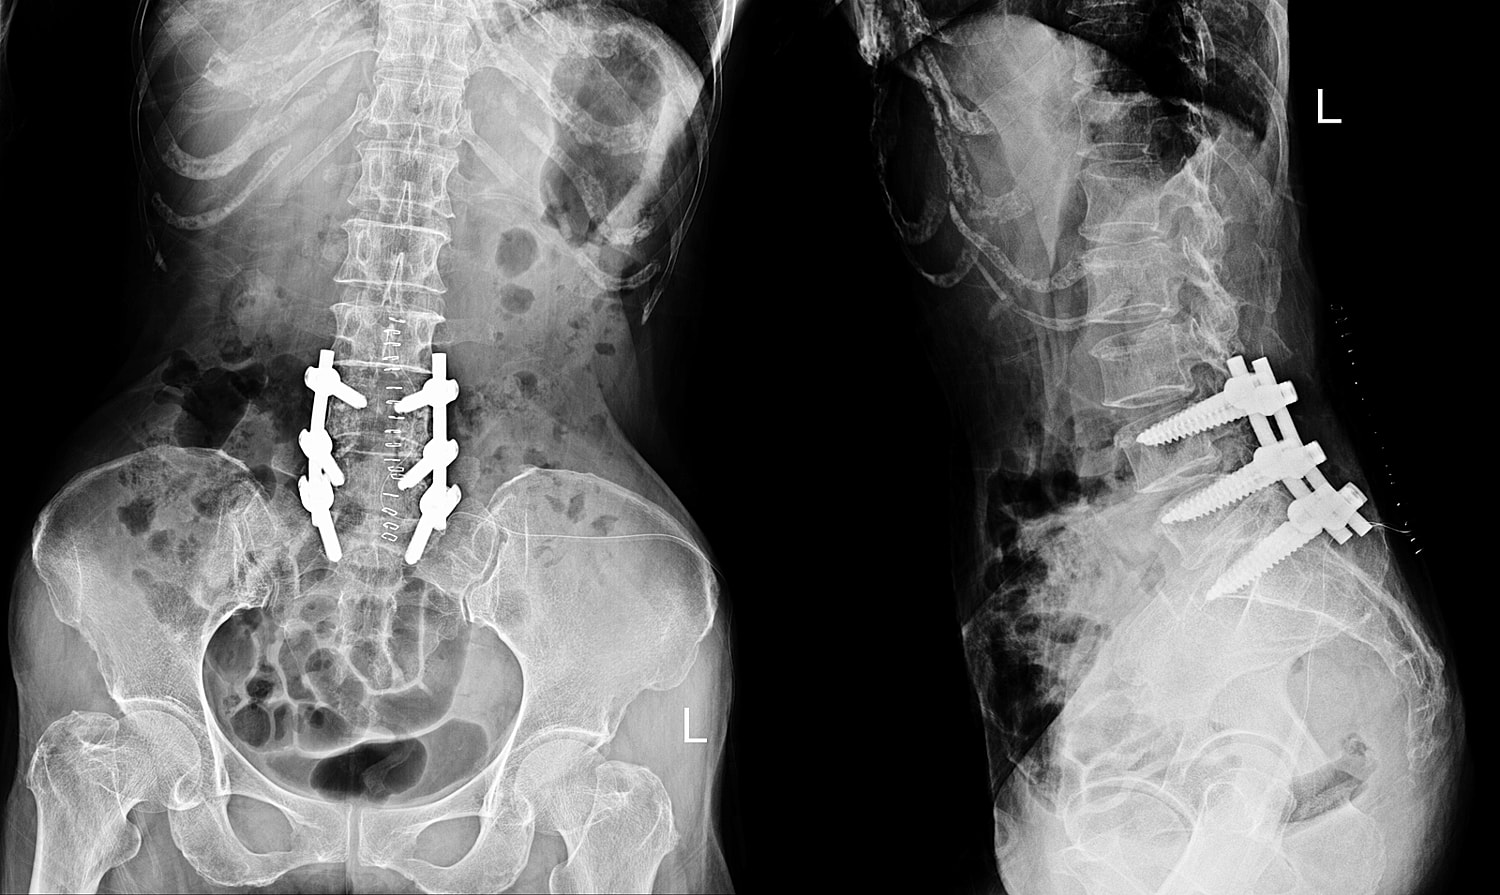

During the surgery, the chosen vertebrae are joined together using either bone grafts, metal rods, or screws. The aim of the surgery is to eliminate any painful movement between the vertebrae by making them into one solid bone. It's often used to correct issues such as spinal deformities, instability, or damage caused by diseases like arthritis or injuries. The approach depends on the affected area of the spine and your specific condition.

Each spine fusion technique uses a different approach to access the spine:

Procedures are performed under general anesthesia, often using advanced navigation or robotic systems to improve accuracy and outcomes.